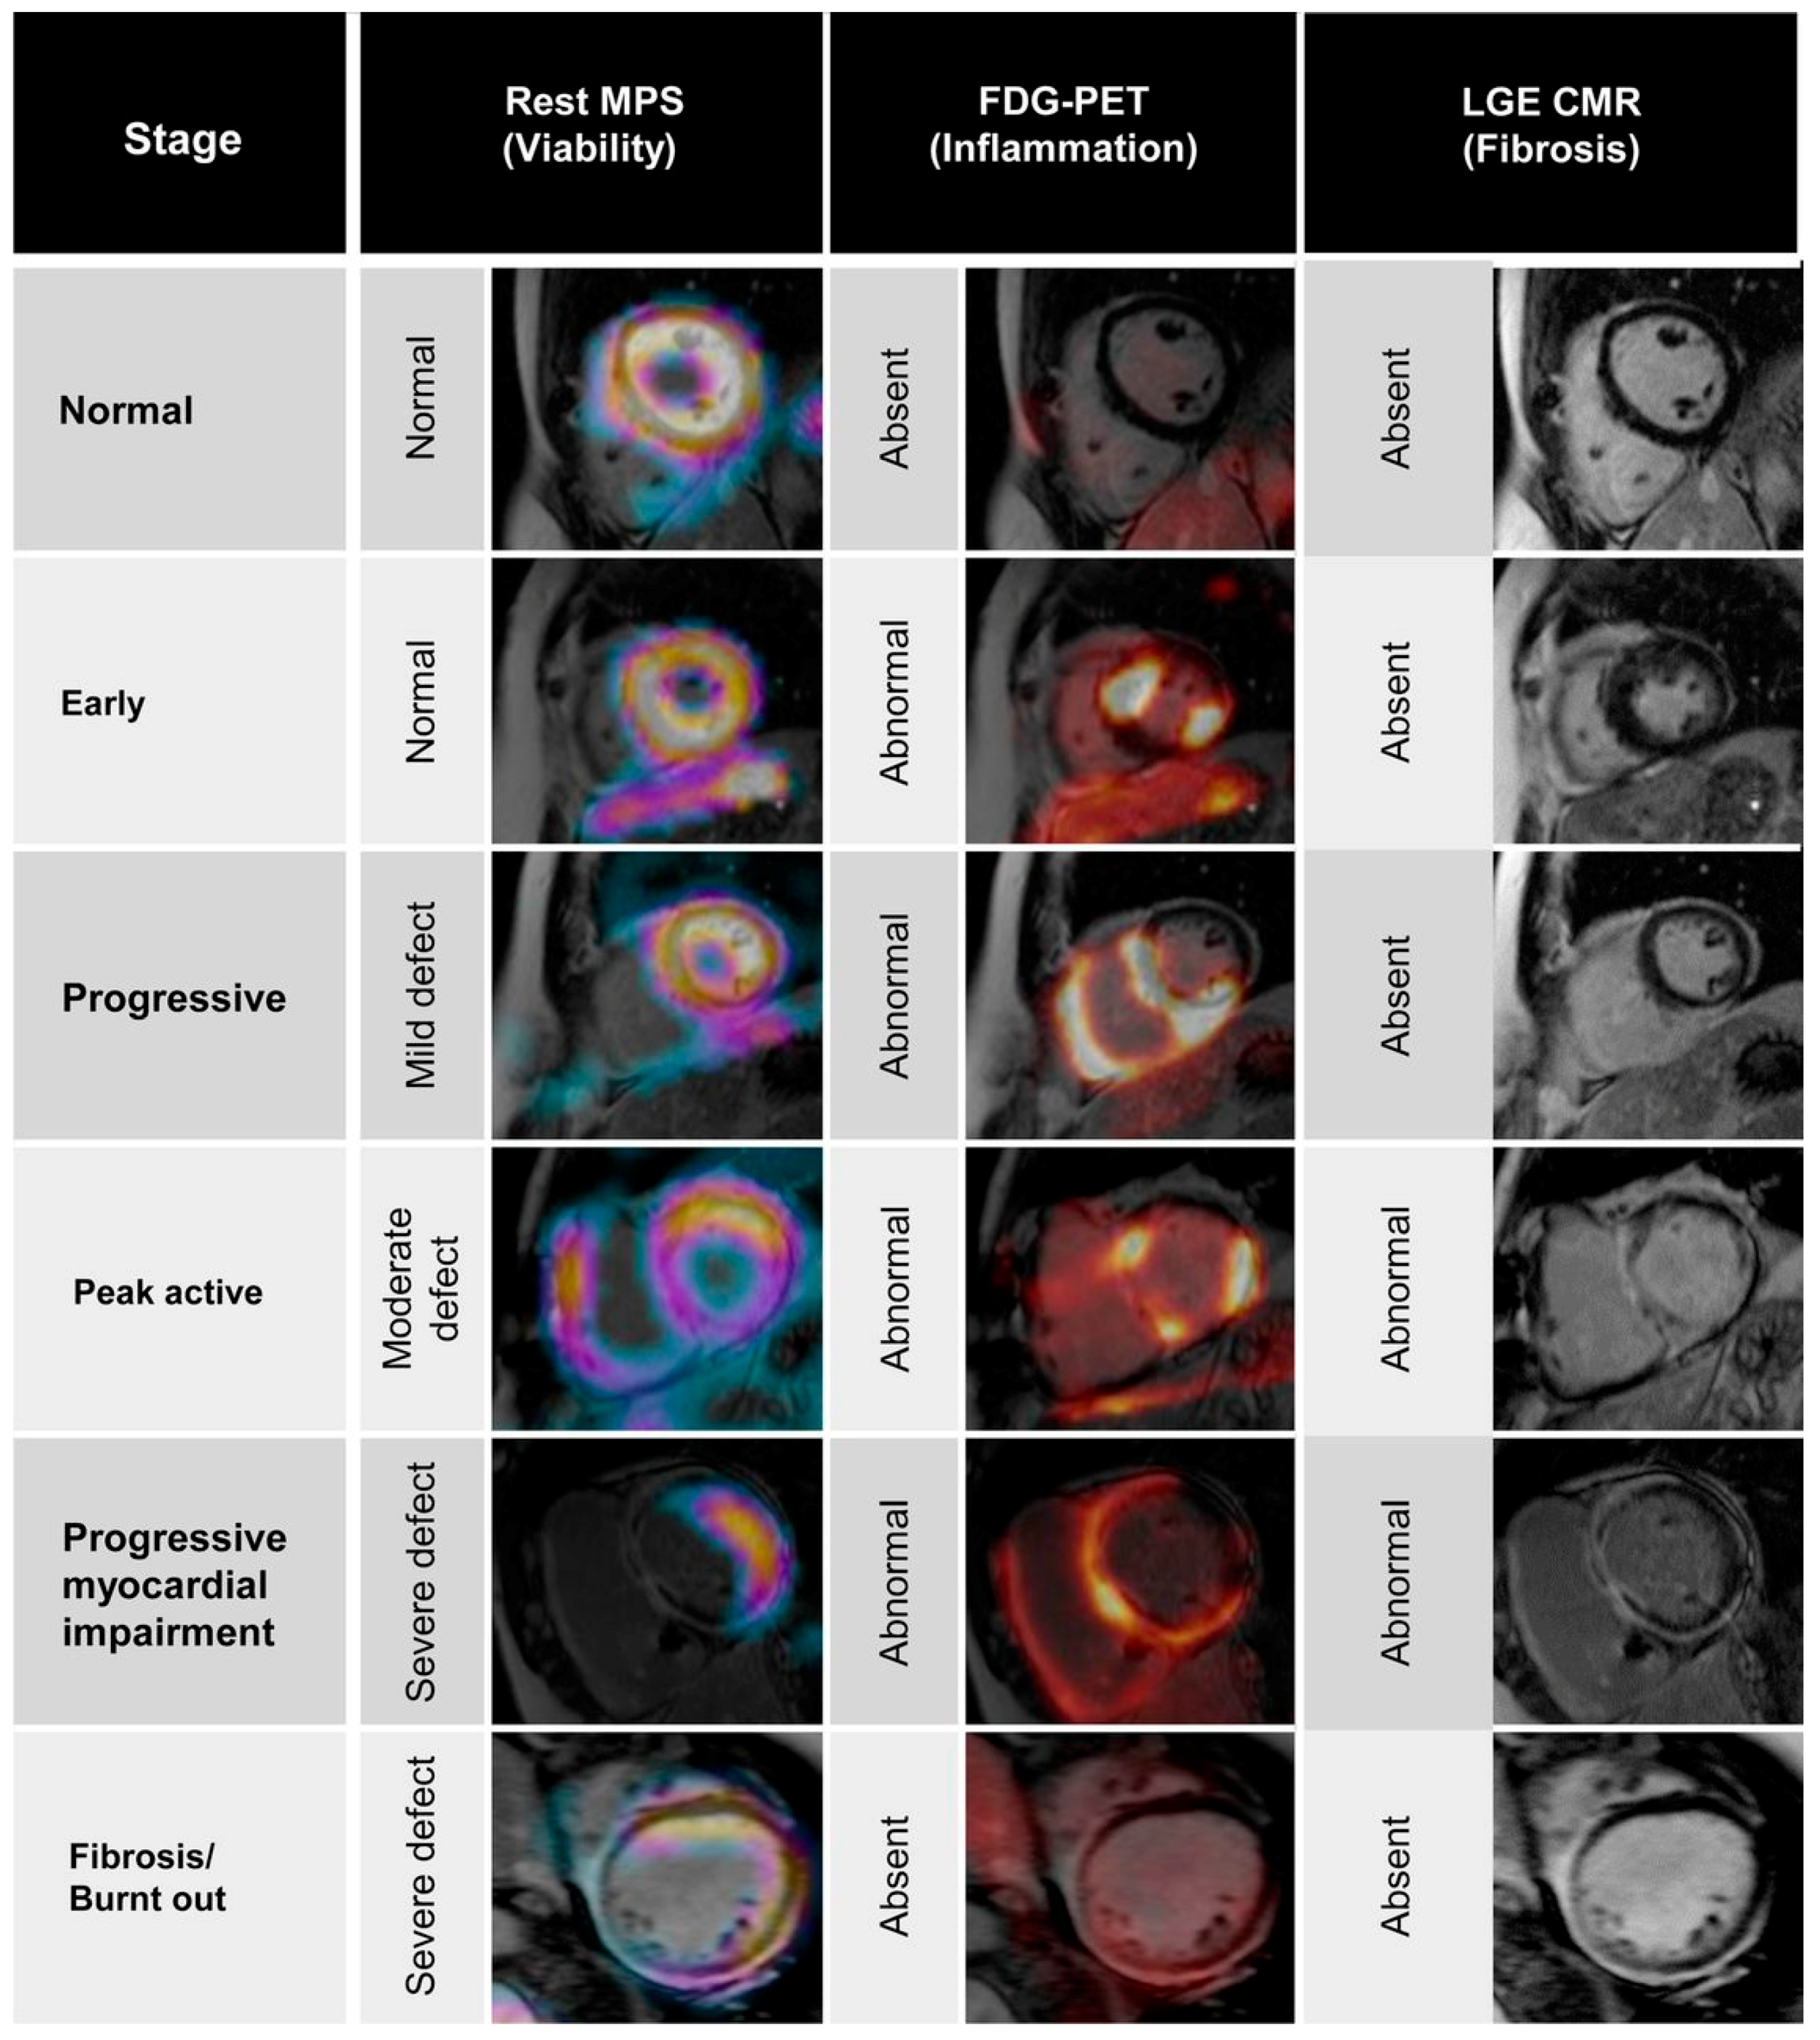

5.4. Infiltrative and Inflammatory Processes